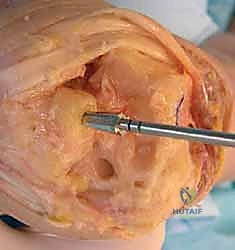

Carpal preparation requires exacting precision. Using the Maestro system as the archetype, the carpal resection guide is positioned to allow resection of 2 to 3 mm of the capitate head. It is provisionally held in position with two 0.062-inch Kirschner wires. The first wire is placed into the capitate neck and the second into the metaphysis of the third metacarpal, ensuring that the guide is perfectly parallel to the third metacarpal axis. With proper placement, the ulnar guide wing will lie close to the triquetrum–hamate articulation, and the radial wing will bisect the scaphoid at its distal third.

With the wrist held in neutral, the radius is scored through the cutting slot in the guide to provide a reference for the distal radial resection. The thumbscrew on the carpal resection guide is loosened to allow insertion of the radial resection guide boom. Following radial resection, the scaphoid, capitate head, hamate edge, and triquetrum are resected at a precise 90-degree angle to the axis of the forearm jig. The trial carpal plate is provisionally determined by the curvature and width of the remaining proximal carpal surface; it must lie flush with the hamate and proximal capitate surfaces. Unlike older designs, it is not always necessary to attempt fusion of the distal pole of the scaphoid to the surrounding carpus. The Maestro Wrist has a provision to replace the entire scaphoid using a carpal plate incorporating a modular radial augment, of which three separate sizes are available.